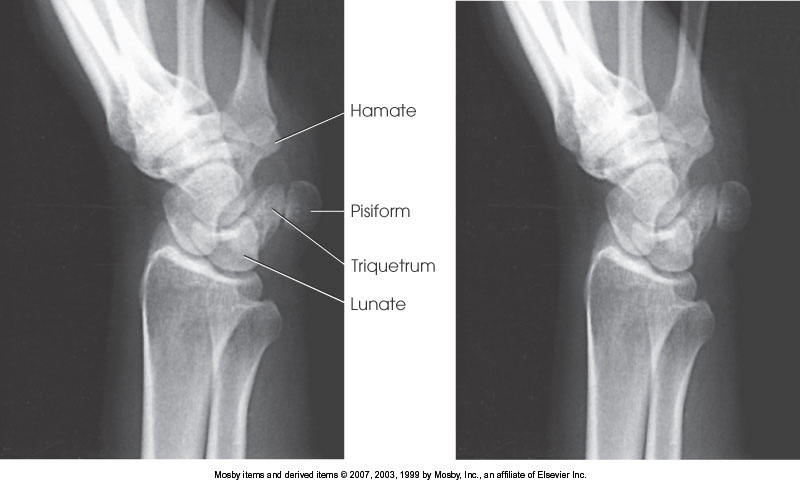

What position is demonstrated?

AP Oblique Wrist